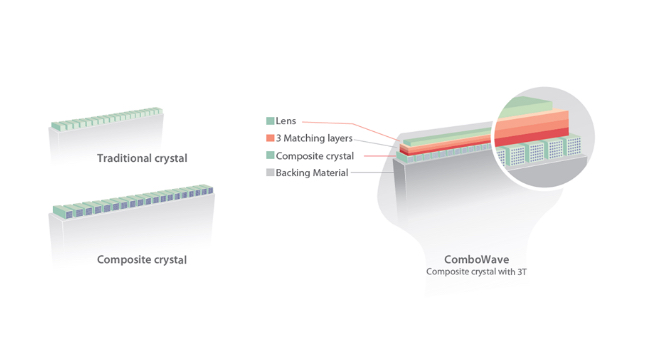

eXpress Clarity

More clarity at handUltra-light volume transducer with superior performance

The ultra-light and high-density volume transducer D8-2E offers superior obstetric imaging performance across 2D, Color and 3D/4D for more diagnostic confidence and patient care.